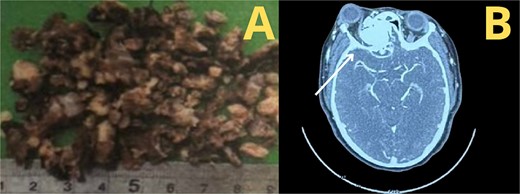

A tomography was performed to assess the extent of the mass inside the right nasal cavity. The imaging findings (Fig. 1) were consistent with a large mass (65 × 44 + 39 mm) originating from the right turbinates that was heavily remodeling the medial wall and the floor of the right orbit, compromising internal aspects of the maxillary and ethmoid bones; leading to a superior lateralization of the right eye causing exophthalmos.

Muscular and neural tissue were conserved intact but displaced.

According to the information gathered, the surgeon decided to perform a partial resection of the maxillary neoplasia (Fig. 2). The chosen approach upon evaluation was the Caldwell–Luc procedure, gaining access to the maxillary sinus. Dimensions and anatomic relationships of the mass were established, determining an extension up to the sphenoid bone covering the ipsilateral choana. A predominantly osseous tumor was observed, with a significant contribution of trabecular bone, vascularized, exhibiting a tendency to hemorrhage. Partial resection of the tumor was accomplished, leading to visualization of the peripheral orbit but not decompressing it totally due to hemodynamic instability during intervention. A residual mass was left at the sphenoidal level and cranial base, a future reintervention was considered.